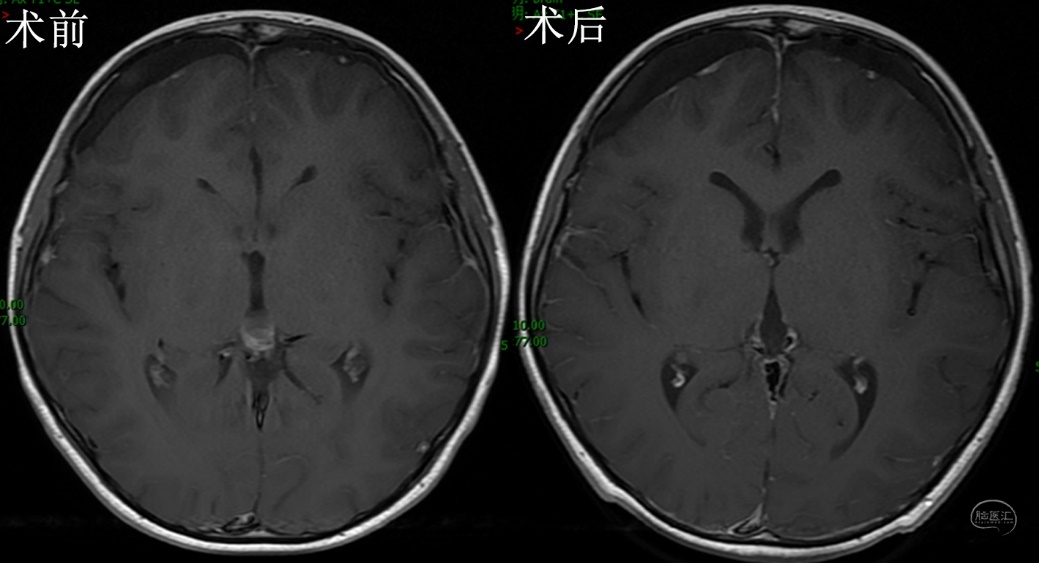

完善术前检查后,在全麻下行内镜下经幕下小脑上入路切除松果体区囊肿。俯卧位,枕下正中切口,骨窗充分暴露窦汇和双侧横窦。剪开、悬吊硬膜,经幕下小脑上探查松果体区,见囊肿位于第三脑室后部,锐性分离周围缘蛛网膜,完整切除囊肿,第三脑室结构清晰可见,保护完好(附视频)。术后MRI示囊肿消失(图2)。患儿恢复良好,无后遗症,1周出院。

图2,术后MRI检查,A、B、C分别为冠矢轴位手术前后增强MRI